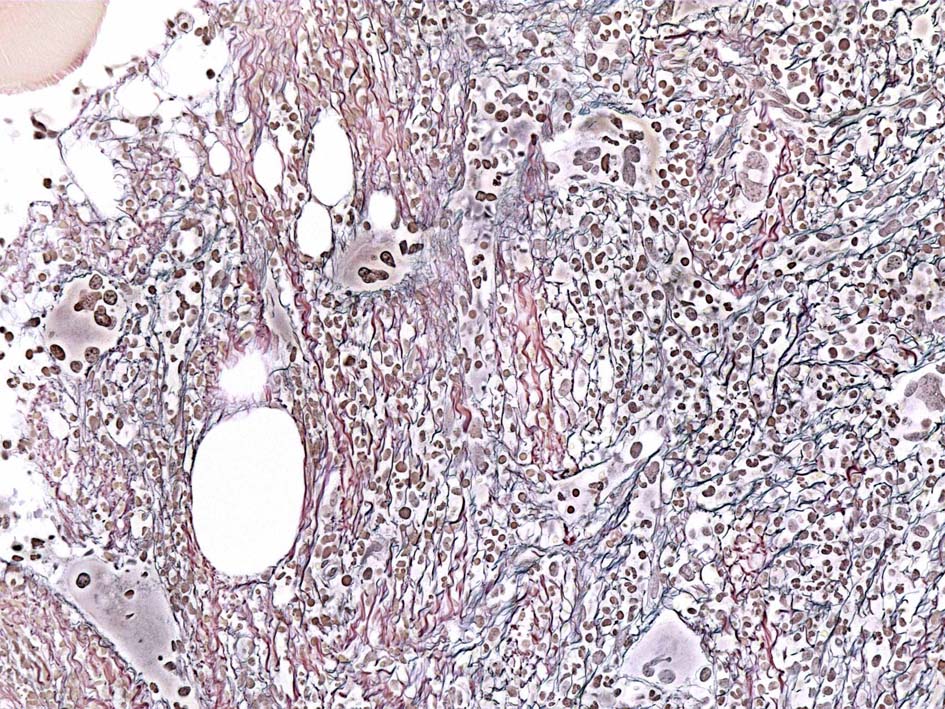

塗銀染色

黒染する弾性線維の増生のほか, 赤く染まる膠原線維の増生が確認される. MF-2 fibrosis. 鍍銀染色の核染色をすると膠原線維の赤染がわからなくなるので行わない.